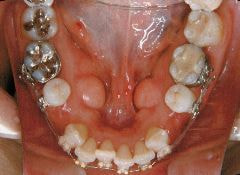

治療例1 (インプラント補綴+矯正)